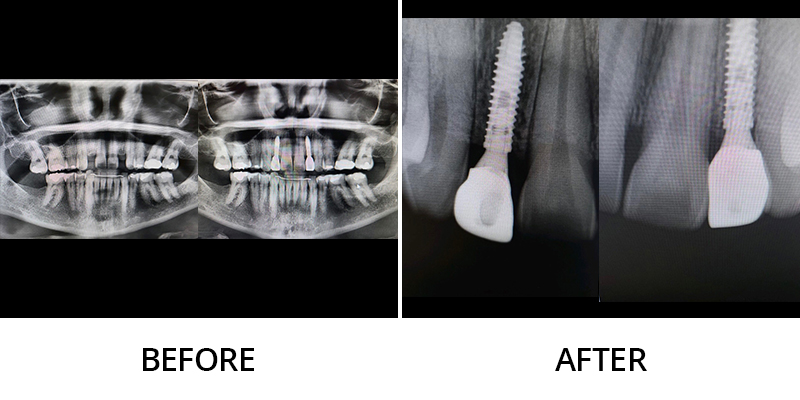

We invite you to explore this smile gallery page to see some of the beautiful results Dr. Kevin Grimm has helped his patients achieve. If you have questions about our dental services, or to schedule your personal consultation with our skilled dentist in Okemos, Michigan, please contact Okemos Smile Center today at 517-349-3110. We look forward to helping you transform your smile!